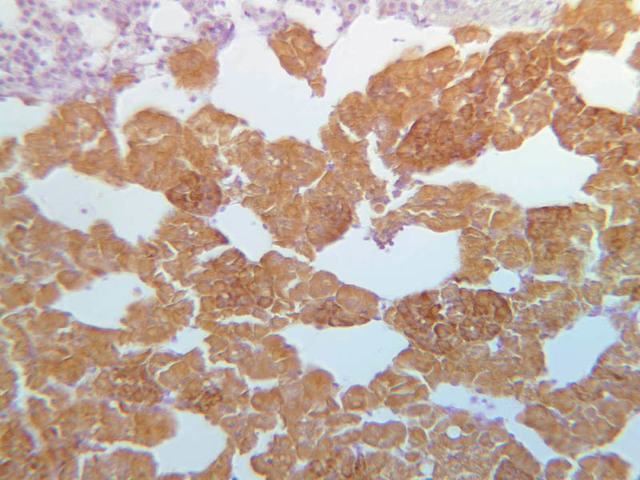

The medulla is composed of large epithelioid cells, arranged in small groups or cords which are separated by blood vessels. Usually, several large veins mark the center of the medulla. When fresh adrenal gland is incubated in solutions of chromium salts (as was the specimen on slide B-61), brownish precipitates form in the cells of the medulla-- hence, the name chromaffin cell (B-61, chromaffin [2.5x, 10x, 20x, 40x] [2.5x, 10x, 20x, 40x-labeled]). The more darkly stained chromaffin cells are known to contain norepinephrine, the less darkly stained cells, epinephrine. In essence, chromaffin cells are specialized postganglionic sympathetic neurons. How does the ultrastructure of these cells differ from that of the secretory cells of the adrenal cortex?